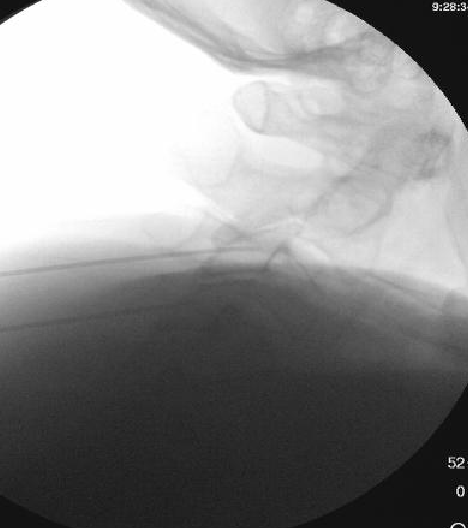

Nasty neuritis. This is 80 degrees 90 seconds.

These images look great. Sorry it happened? Steroid?

Lyrica Rx sent in, and we're starting it for chronic pain (and neuritis). She gets a shoulder scope in two weeks for a large RCT. I like antineuropathics (gabapentin 100mg HS or BID) perioperatively in general. I wish they were given 2 weeks before and after ALL orthopedic surgeries.

Dexamethasone given before RFA needles were removed.